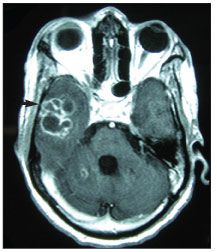

Figure 2. CT scan of the brain demonstrating a right temporal ring-enhancing lesion and vasogenic edema.

A CT scan of the brain demonstrated a right temporal ring-enhancing lesion with vasogenic edema and mass effect but without midline shift (Figure 2). Cerebrospinal fluid examination showed 9 white blood cells/µL (normal, 0 to 5), 126 red blood cells/µL (normal, 0), glucose level of 35 mg/dL (normal, 40 to 70), and total protein level of 283 mg/dL (normal, 15 to 45). Results of India ink analysis were negative.